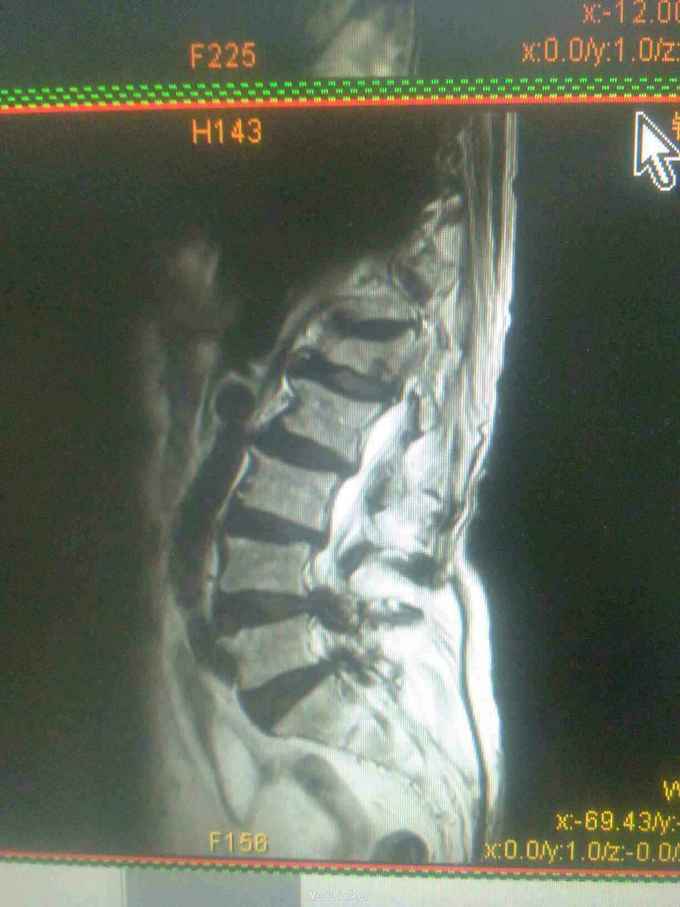

患者女,71岁,因双下肢无力,活动障碍5年余,不能行走半年。患者自诉于5年前无明显原因及诱因下逐渐出现双下肢无力,开始以双足部、双小腿为主,后整个下肢都感到无力,到入院半年前不能站立行走。大小便功能正常。

查体,双下肢肌肉萎缩,肌张力高,双侧大腿肌力3级,双小腿肌力2级,双足部肌力0级,双足部疼觉减退,会阴及双大腿、小腿感觉均正常,腱反射未引出,肛门反射、腹壁反射可引出,肛门括约肌未见松驰,双上肢查体正常。

目前诊断:双下肢瘫痪查因。

请教各位同行老师,这个考虑是什么问题,需要进一步完善什么检查。